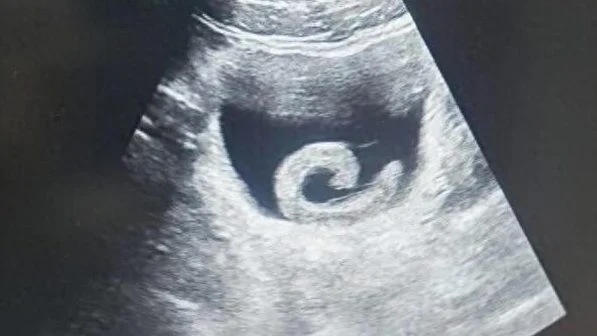

Hình ảnh siêu âm cho thấy một con đỉa sống trong bàng quang của người đàn ông ở Trịnh Châu, Trung Quốc, trước khi được các bác sĩ tiến hành phẫu thuật lấy ra. Ảnh: O.C

Con đỉa đã gây ra cho Zheng những cơn đau dữ dội đến mức anh không còn lựa chọn nào khác ngoài việc đến phòng cấp cứu của một bệnh viện địa phương. Khi nghe lý do, các bác sĩ không khỏi sửng sốt. Kết quả siêu âm xác nhận đúng như anh trình bày: một con đỉa sống đang ở trong bàng quang. Ngay lập tức, các bác sĩ chuẩn bị cho ca phẫu thuật khẩn cấp nhằm loại bỏ ký sinh trùng và cứu mạng bệnh nhân.